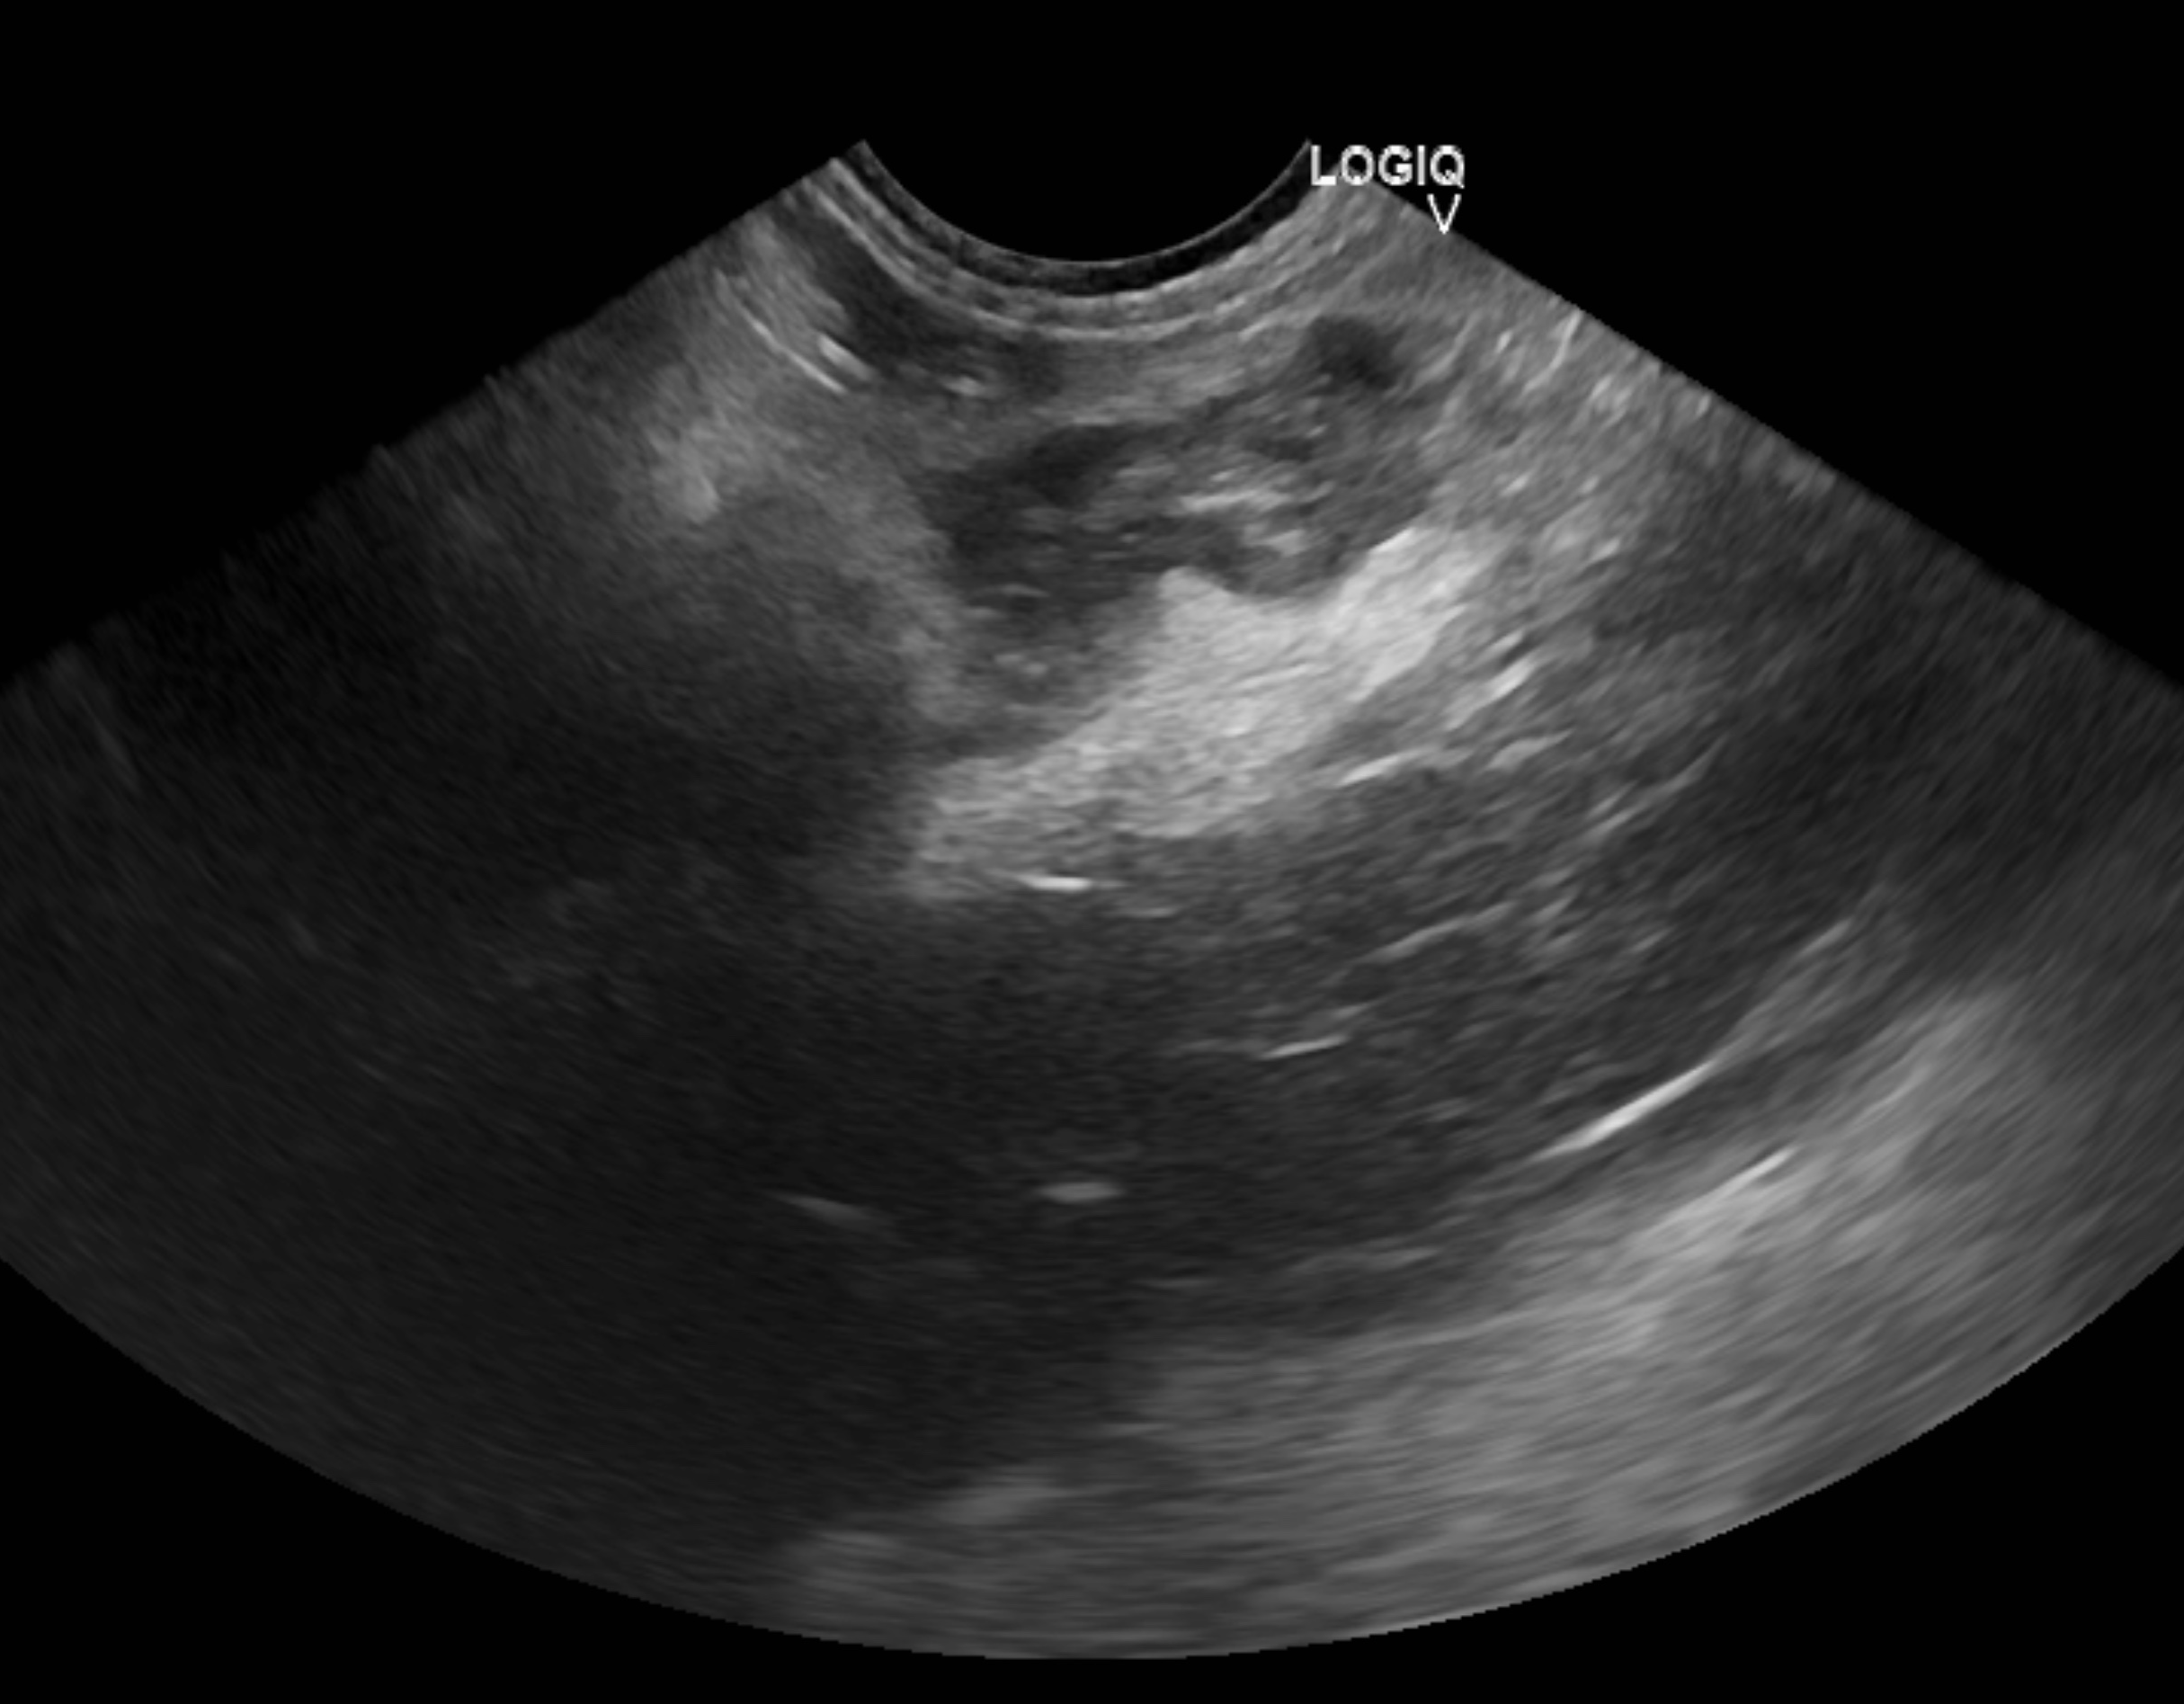

6-2.超音波検査

猫の膵炎が疑われる場合の最も一般的な検査です。

膵臓だけではなく、腸や肝臓、胆嚢なども一緒に評価できます。

一方で正常な膵臓と急性膵炎や慢性膵炎との区別、

腫瘤がある場合の腫瘍と過形成との区別といった際の特異度は高くはありません。

猫の急性膵炎の超音波検査所見は、あいまいな場合もあれば、膵臓の肥大、周囲の腸間膜の高エコー、

限局性の腹部滲出液などを認める場合もあります。

慢性膵炎の超音波検査の特徴は猫では十分に確立されていません。

膵臓の高エコーまたは混合エコー所見、総胆管の拡張、膵臓腫大、

及び不規則な膵臓の辺縁などが認められる場合があります。